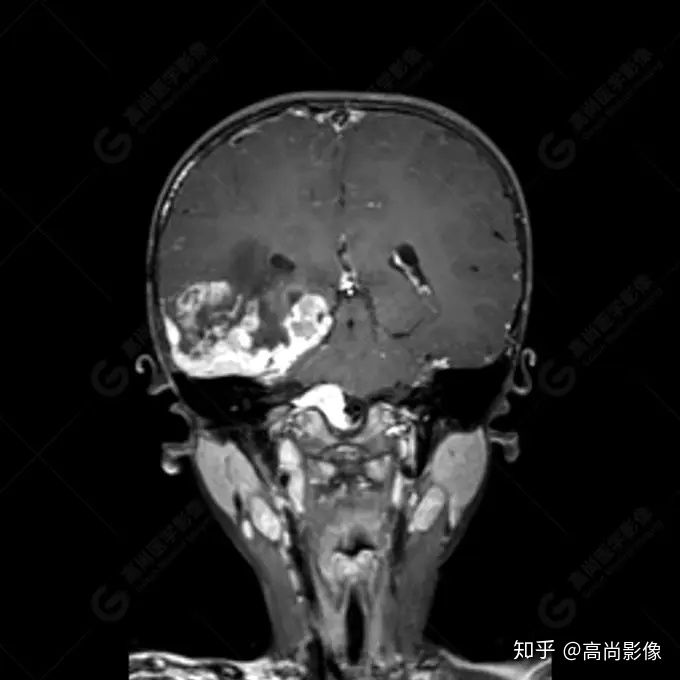

右側(cè)顳葉腫瘤切除術(shù)后(具體不詳):右側(cè)顳部骨質(zhì)不連續(xù)呈術(shù)后改變,右側(cè)顳葉術(shù)區(qū)見片狀長T1長T2信號(hào)影,F(xiàn)LAIR呈低信號(hào);術(shù)區(qū)后方右側(cè)顳枕葉見一巨大占位性病變影,邊界欠清,大小約6.2×5.8×4.3cm(前后×左右×上下),信號(hào)不均勻,T1WI呈等稍低信號(hào)間雜少許高信號(hào),T2WI呈高稍低混雜信號(hào),DWI示部分病灶彌散受限,相應(yīng)ADC圖減低,磁敏感序列見部分呈極低信號(hào),增強(qiáng)掃描可見明顯不均勻強(qiáng)化,鄰近硬腦膜及小腦幕增厚并明顯強(qiáng)化;另延髓右前方及右側(cè)橋小腦角區(qū)見一不規(guī)則形異常信號(hào)影,大小約3.2×1.3×3.7cm(左右×前后×上下),呈長T1稍長T2信號(hào),F(xiàn)LAIR呈等信號(hào),DWI未見受限,增強(qiáng)后明顯均勻強(qiáng)化,鄰近腦膜明顯強(qiáng)化。鄰近腦實(shí)質(zhì)及右側(cè)顳角明顯受壓;左側(cè)大腦半球未見局灶性信號(hào)異常,中線結(jié)構(gòu)稍左移。

右側(cè)顳葉腫瘤切除術(shù)后:現(xiàn)術(shù)區(qū)后方右側(cè)顳枕葉及延髓右前方占位,右側(cè)顳枕部硬腦膜及小腦幕明顯強(qiáng)化,結(jié)合既往影像資料,考慮為胚胎源性惡性腫瘤,如非典型畸胎樣/橫紋肌樣瘤(AT/RT)或原始神經(jīng)外胚層腫瘤(PNET)。